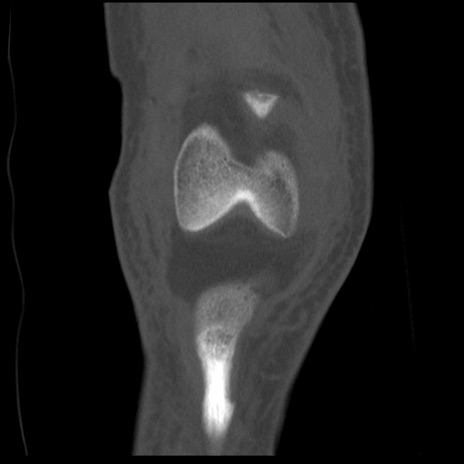

右膝関節CT

矢状断像